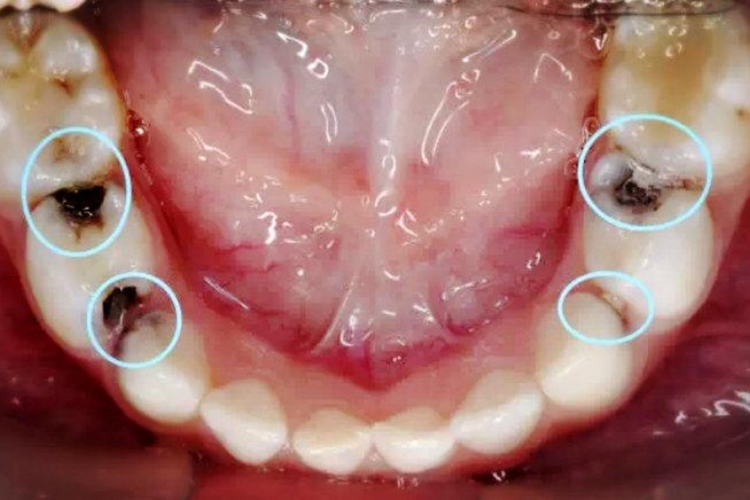

邻面龋齿是发生在牙的近远中面的龋病,初期时累及牙表层牙釉质,表现为硬组织发生脱矿,微晶结构改变,牙釉质透明度下降,致使牙釉质呈白垩色。继之病变部位有色素沉着,局部可呈黄褐色或棕黄色。随着组织脱矿、有机质破坏分解的不断进行,牙釉质和牙本质会逐渐软化,釉质龋损变色区有粗糙感,失去原有的光滑度,最终发生牙体缺损,形成龋洞。